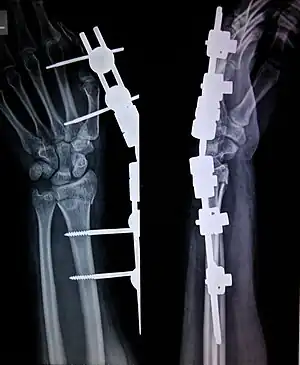

External fixation is a surgical treatment wherein Kirschner pins and wires are inserted and affixed into bone and then exit the body to be attached to an external apparatus composed of rings and threaded rods — the Ilizarov apparatus, the Taylor Spatial Frame, and the Octopod External Fixator — which immobilises the damaged limb to facilitate healing.[1] As an alternative to internal fixation, wherein bone-stabilising mechanical components are surgically emplaced in the body of the patient, external fixation is used to stabilize bone tissues and soft tissues at a distance from the site of the injury.

In this kind of reduction, holes are drilled into uninjured areas of bones around the fracture and special bolts or wires are screwed into the holes. Outside the body, a rod or a curved piece of metal with special ball-and-socket joints joins the bolts to make a rigid support. The fracture can be set in the proper anatomical configuration by adjusting the ball-and-socket joints. Since the bolts pierce the skin, proper cleaning to prevent infection at the site of surgery must be performed.

Installation of the external fixator is performed in an operating room, normally under general anesthesia. Removal of the external frame and bolts usually requires special wrenches and can be done with no anesthesia in an office visit.